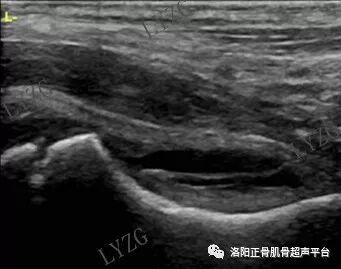

双侧对比,右髋关节前隐窝内团声状中等回声增生滑膜,未见明显积液;左髋关节前隐窝内未见明显积液及滑膜增生

左髋关节前隐窝内积液并滑膜增生(呈条带状)

双侧对比,右髋前隐窝内积液,未见明显滑膜增生;左髋关节前隐窝内未见大于2mm积液,未见明显滑膜增生